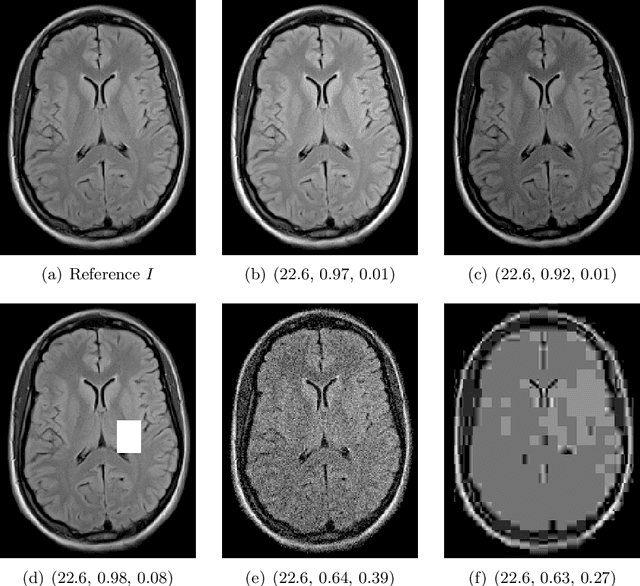

Abstract:Image quality assessment (IQA) is standard practice in the development stage of novel machine learning algorithms that operate on images. The most commonly used IQA measures have been developed and tested for natural images, but not in the medical setting. Reported inconsistencies arising in medical images are not surprising, as they have different properties than natural images. In this study, we test the applicability of common IQA measures for medical image data by comparing their assessment to manually rated chest X-ray (5 experts) and photoacoustic image data (1 expert). Moreover, we include supplementary studies on grayscale natural images and accelerated brain MRI data. The results of all experiments show a similar outcome in line with previous findings for medical imaging: PSNR and SSIM in the default setting are in the lower range of the result list and HaarPSI outperforms the other tested measures in the overall performance. Also among the top performers in our medical experiments are the full reference measures DISTS, FSIM, LPIPS and MS-SSIM. Generally, the results on natural images yield considerably higher correlations, suggesting that the additional employment of tailored IQA measures for medical imaging algorithms is needed.

Abstract:Image quality assessment (IQA) is not just indispensable in clinical practice to ensure high standards, but also in the development stage of novel algorithms that operate on medical images with reference data. This paper provides a structured and comprehensive collection of examples where the two most common full reference (FR) image quality measures prove to be unsuitable for the assessment of novel algorithms using different kinds of medical images, including real-world MRI, CT, OCT, X-Ray, digital pathology and photoacoustic imaging data. In particular, the FR-IQA measures PSNR and SSIM are known and tested for working successfully in many natural imaging tasks, but discrepancies in medical scenarios have been noted in the literature. Inconsistencies arising in medical images are not surprising, as they have very different properties than natural images which have not been targeted nor tested in the development of the mentioned measures, and therefore might imply wrong judgement of novel methods for medical images. Therefore, improvement is urgently needed in particular in this era of AI to increase explainability, reproducibility and generalizability in machine learning for medical imaging and beyond. On top of the pitfalls we will provide ideas for future research as well as suggesting guidelines for the usage of FR-IQA measures applied to medical images.